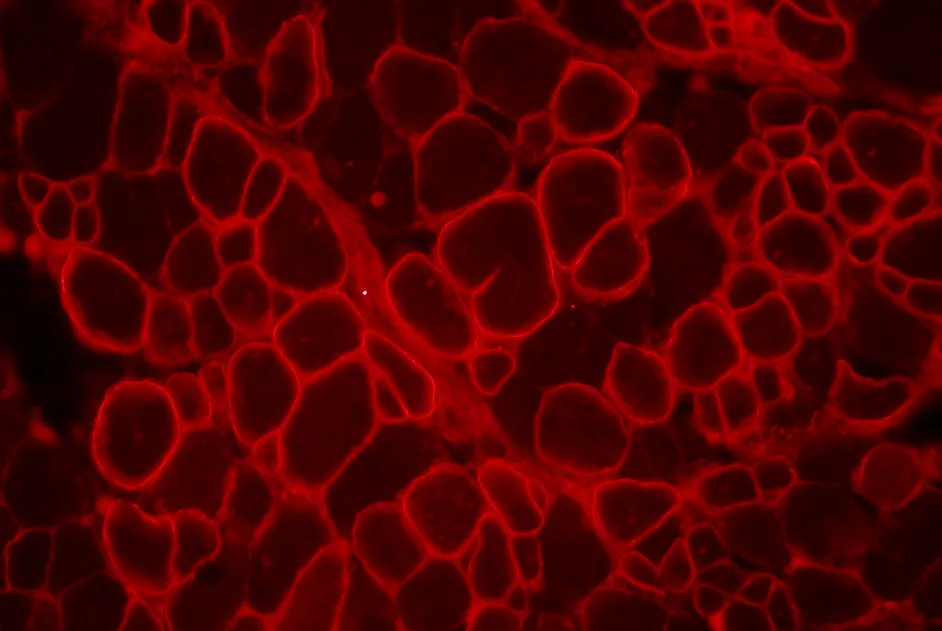

Le Glybera devient le premier médicament de thérapie génique autorisé en Europe

A compter de l’été 2013, les malades affectés par un déficit en lipoprotéine lipase (LPL) disposeront d’un médicament de thérapie génique préventif contre les attaques pancréatiques graves et régulières.